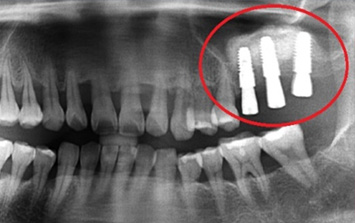

아래턱 어금니 발치 후 장시간 방치하여 잇몸 뼈 소실이 심한 상태로 내원. 뼈 이식 후 임프란트를 식립하였습니다.

뼈 이식 후 치조골 밀도가 높아진 모습